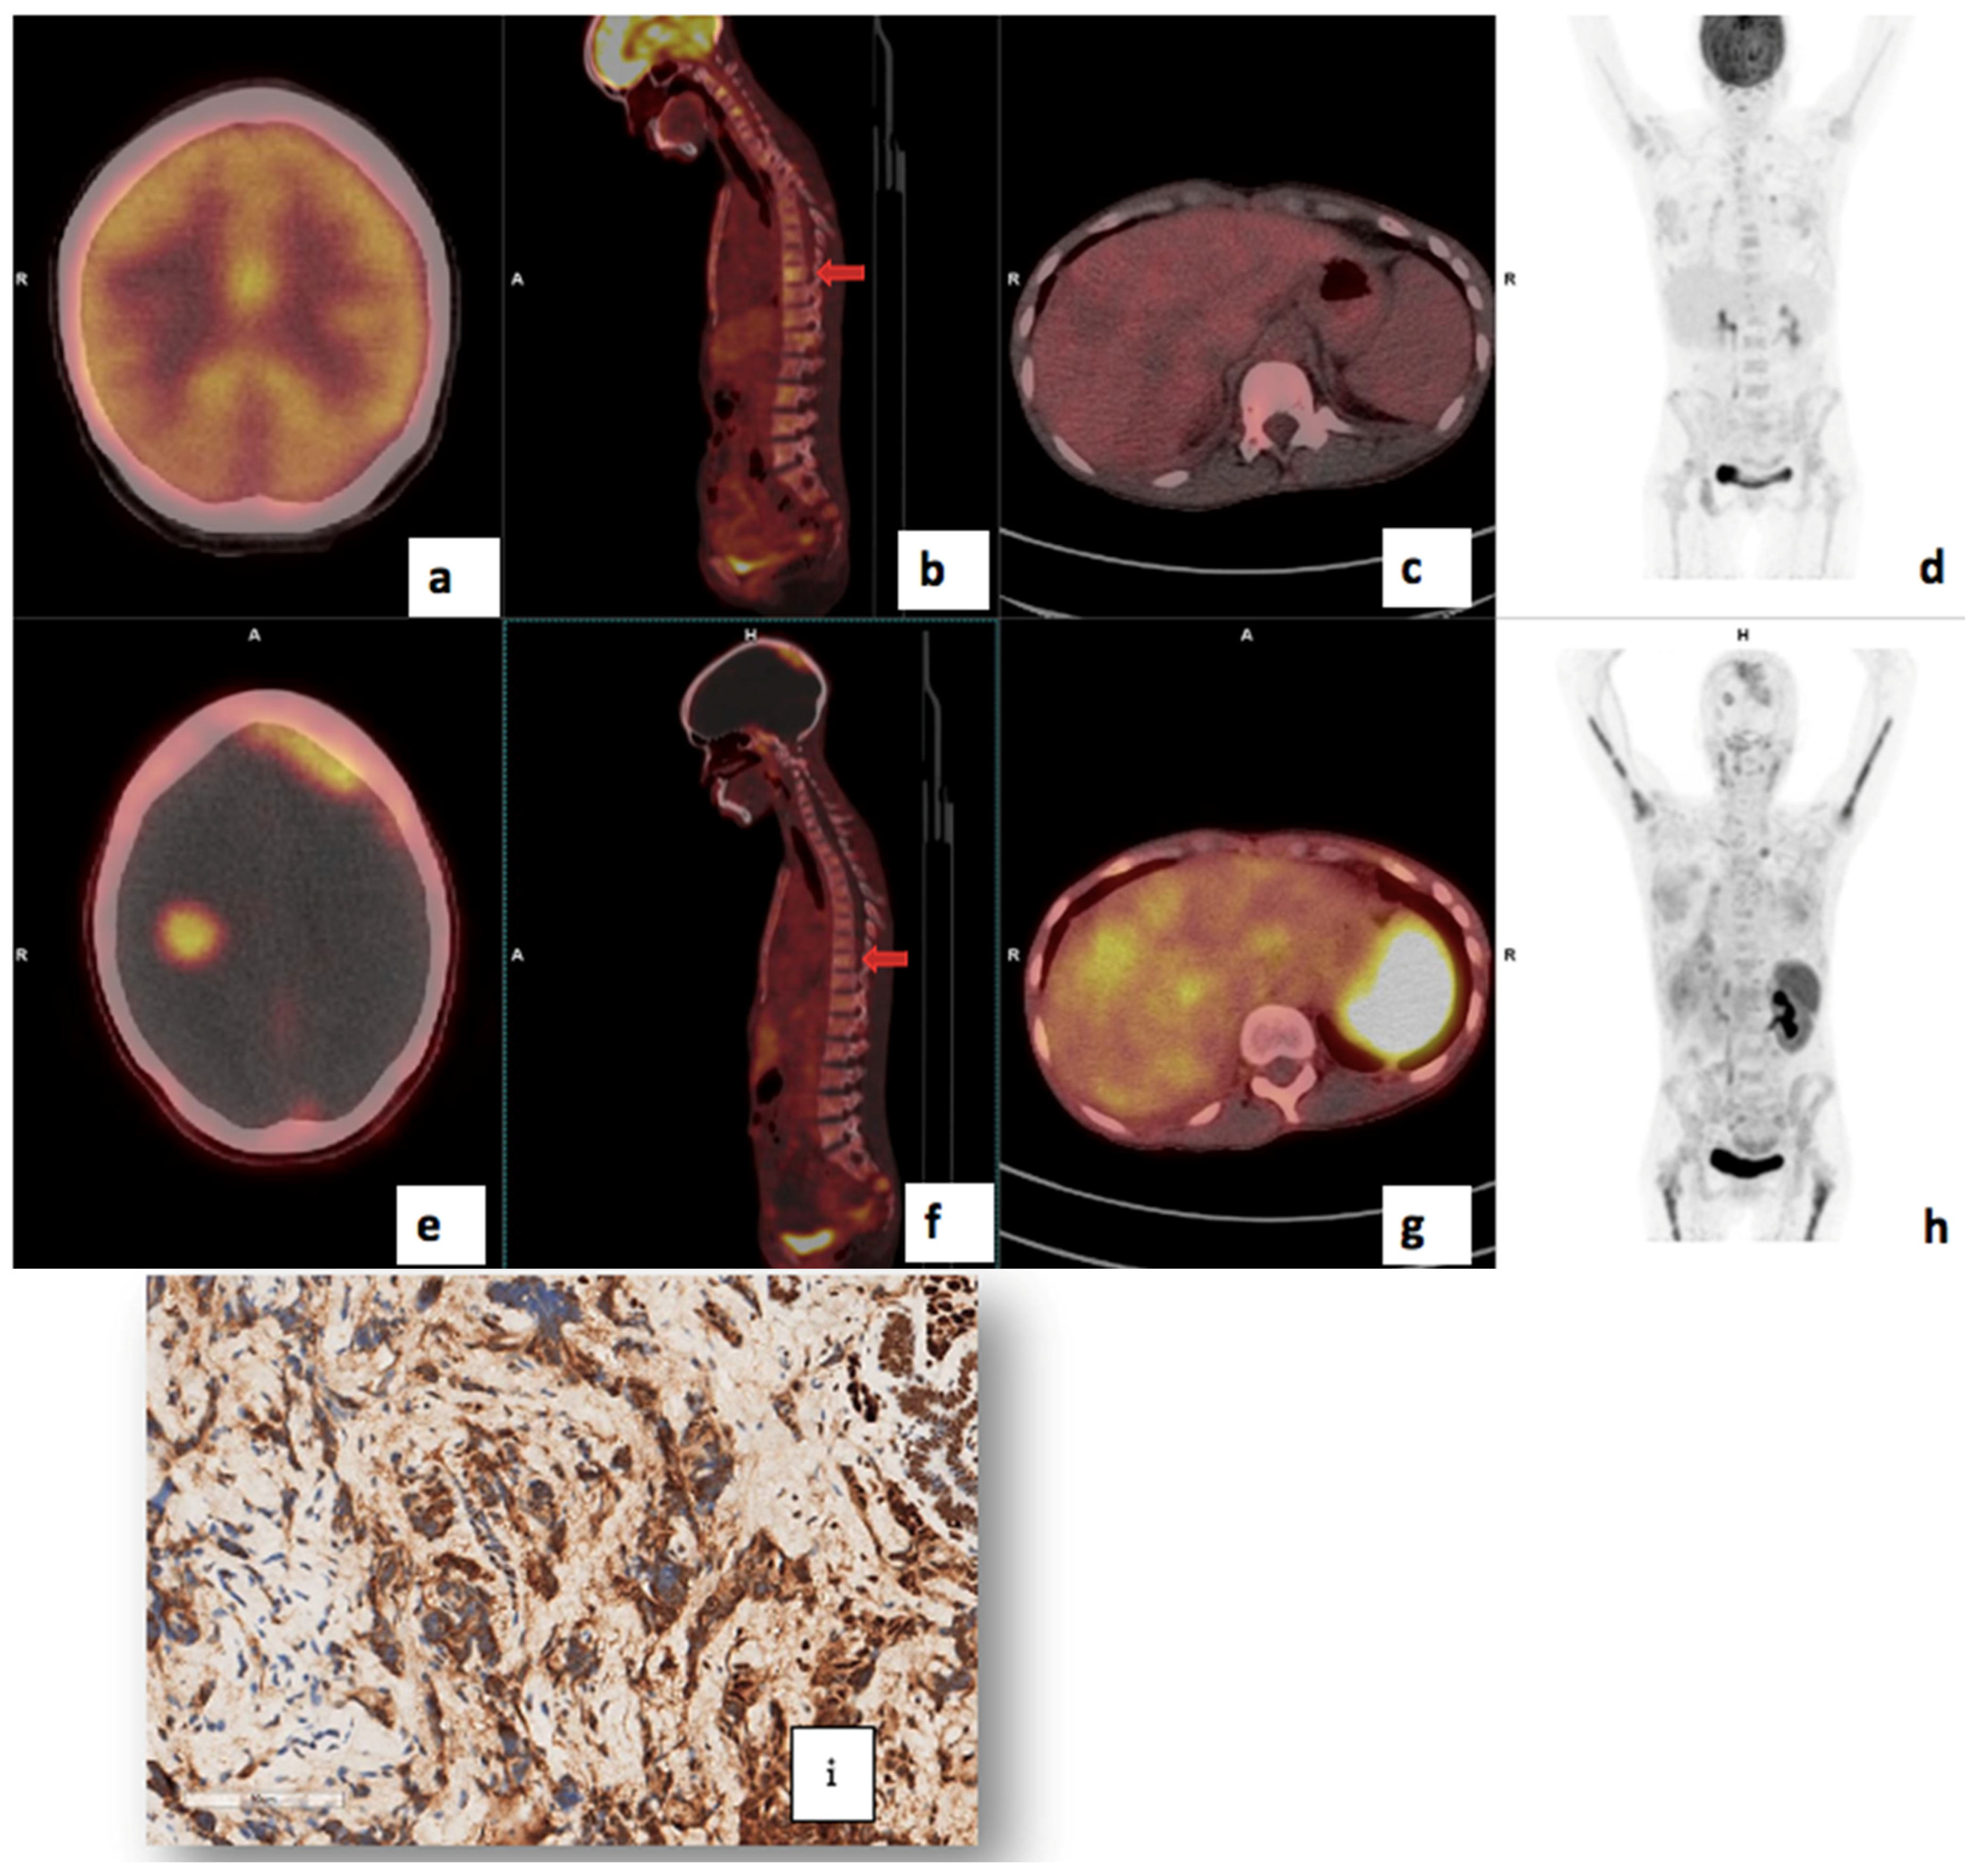

3.4. Visual Analysis

3.7. Correlation of PET/CT Metrics with CXCR4 Immunohistochemistry Staining